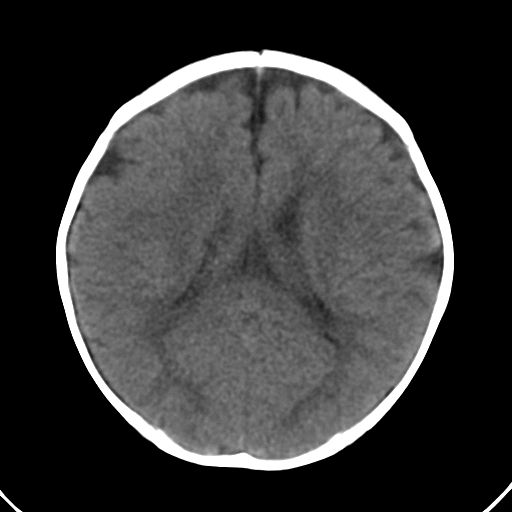

男,10月,足月剖腹产,无缺氧病史,当时评分均正常,学走路时脚后跟不着地!

小孩子片子,看得少,请各位老师看看有问题没?

未见明显异常。

外部性脑积水

考虑外部性脑积水

轻度脑外脑积水表现.